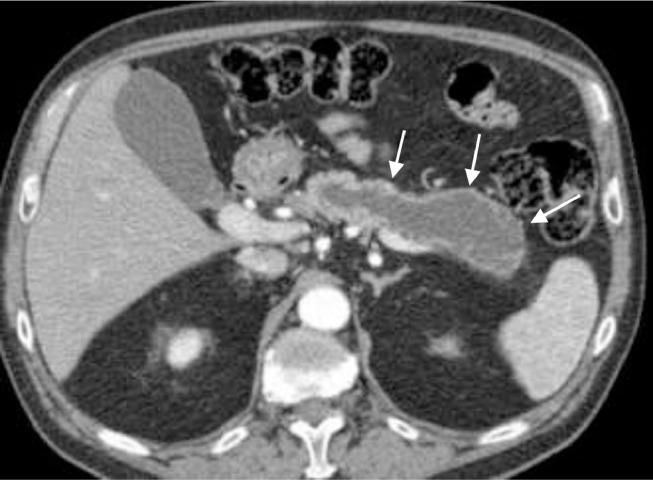

Intraductal papillary mucinous neoplasm complicated by a gastropancreatic fistula.

One of the rare complications of low-grade pancreatic neoplasms is fistulization into nearby structures. This often does not present clinically, but is incidentally identified in patients who have been imaged serially to monitor the progression of the disease. In this report, we present an uncommon complication of an intraductal papillary mucinous neoplasm, which developed a spontaneous gastropancreatic fistula in a patient who was conservatively managed. The clinical course, imaging features, and management of this case are discussed.